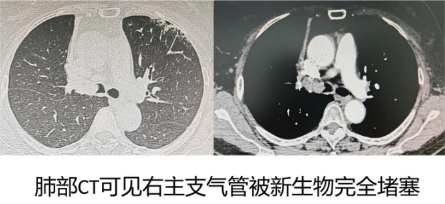

57岁的赵女士(化名)因持续3个多月的剧烈干咳、痰中带血伴气短辗转多家医院,最终慕名来到哈医大一院群力呼吸科寻求帮助。肺部CT显示,其右主支气管被一枚新生物阻塞。患者咳嗽剧烈,呼吸困难明显,日常活动严重受限,查体发现右肺呼吸音极弱,若不及时干预,随时可能因严重呼吸困难缺氧危及生命。